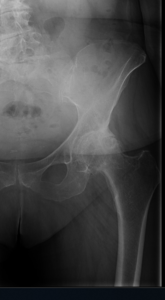

Diagnosis is made by evaluating medical history, physical examination and X-rays.

- Osteoarthritis: It is characterized by progressive wearing away of the cartilage of the joint. As the protective cartilage wears down, the bone ends rub against each other and cause pain in the hip. Rheumatoid arthritis: This is an autoimmune disease in which the tissue lining the joint (synovium) becomes inflamed, resulting in the production of excessive joint fluid (synovial fluid). This leads to loss of cartilage causing pain and stiffness.

- Traumatic arthritis: This is a type of arthritis resulting from a hip injury or fracture. Such injuries can damage the cartilage and cause hip pain and stiffness over a period of time.

The most common symptom of hip arthritis is joint pain and stiffness resulting in limited range of motion. Vigorous activity can increase the pain and stiffness which may cause limping while walking.